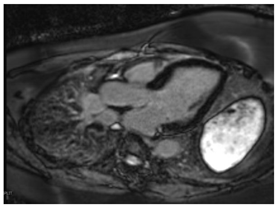

In addition to providing an accurate structural and functional assessment of cardiac chambers in IOC, CMR can quantify cardiac iron overload. Stored iron molecules in the form of hemosiderin act as small magnets when placed in a strong magnetic field, which shortens the relaxation time of tissue protons by disrupting their coherence. This can be measured more specifically as a T2*, which is the half-life time of signal intensity decay obtained using a gradient echo rather than a spin echo in T2 []. T2* is inversely proportional to the tissue iron contact. T2* measured within the interventricular septum is considered highly representative of global myocardial iron and has prognostic implications, as discussed below [,,].

T1 mapping is complementary to T2* and was shown to be concordant []. Native T1 time will be shortened with iron overload. Studies suggest that while T1 time may be more sensitive for cardiac iron content, it is less specific as it can be affected by myocardial fibrosis and fat [,]. Patchy areas of LGE can be seen secondary to replacement fibrosis []. In individuals with β-thalassemia major and myocardial iron overload, ECV was found to be increased and associated with a history of heart failure []. Key CMR findings in IOC are summarized in Table 3.